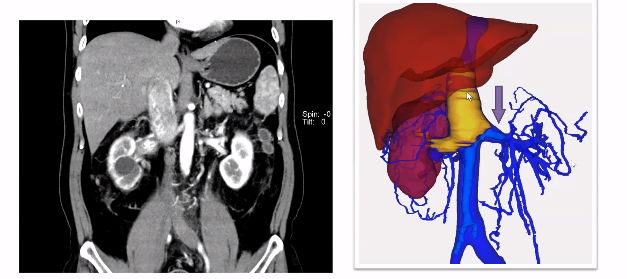

从开放翻肝到DOPI转变

在传统的瘤栓手术中,右侧肾癌合并Mayo II-III级下腔静脉瘤栓往往需要充分离断肝脏韧带并将肝脏“翻起”以扩展手术空间,依次阻断下腔静脉远心端、左肾静脉及下腔静脉近心端后进行瘤栓切除手术。对于III级瘤栓,还需要阻断第一肝门血管并阻断肝上下腔静脉。操作不仅耗时长,而且难度打,需要很多操作技巧。

下腔静脉近心端不阻断技术则是在不“翻”肝,仅离断右肝三角韧带,不阻断下腔静脉近心端,依靠术中升高气腹压力(12mmHg至20mmHg)阻止近心端血液流出的方式下进行瘤栓切除手术。对于III级瘤栓,该技术可实现在不阻断第一肝门血管的条件下切除瘤栓,降低肝脏缺血再灌注损伤风险。